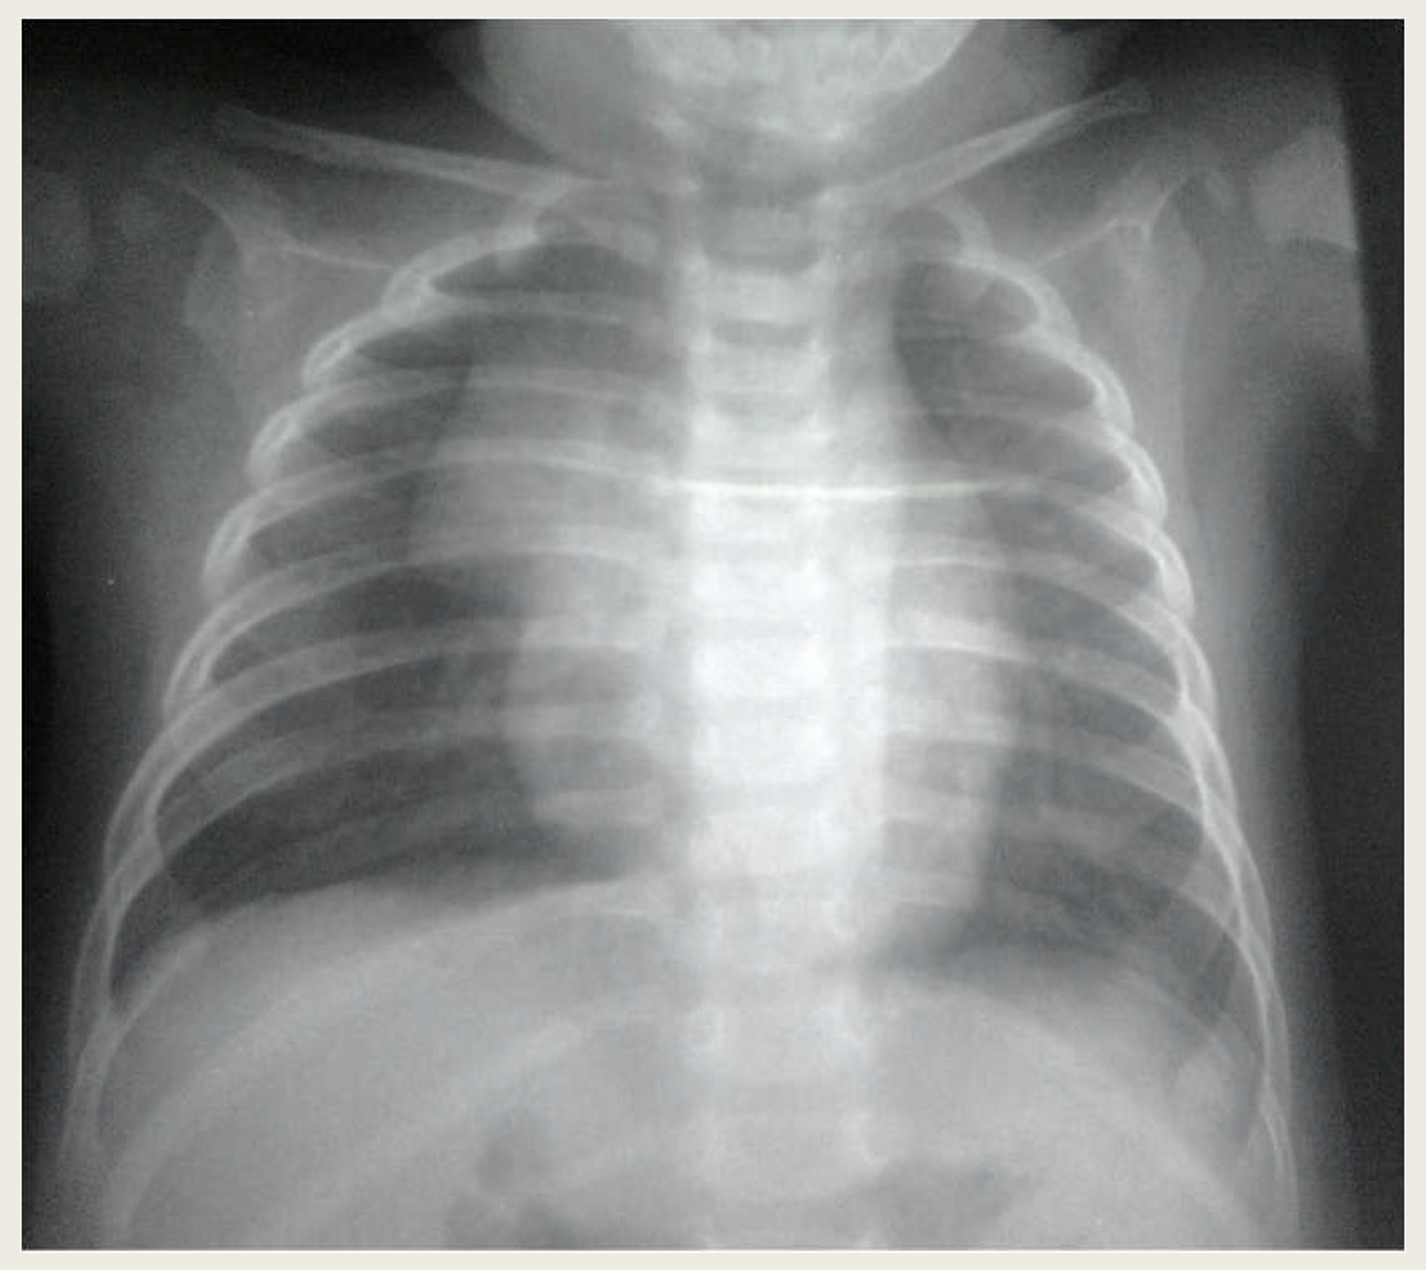

Xquang ngực trẻ em